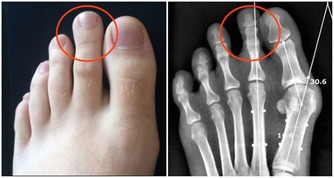

醫生幫他做了檢查,確定他的耳鼓出現破裂,醫生問他是不是最近發生了撞擊?

如果把這部分空氣憋回去,壓力就會轉移到你身體的另一個部位——耳朵。

如果經常這樣做,結果就是耳鼓破裂、中耳炎等疾病,不僅聽力受損還會經常出現頭暈。